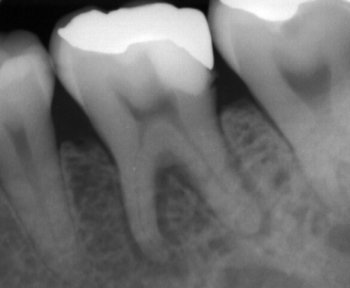

例えばこのレントゲン、

神経が通る穴、根管は左が湾曲し、右が根尖で右に振っています。

さらにやっかいなのが根管が異常に細いことです。

この根管を初めに示したような器具だけでは到底治療は上手くいきません。

そこで最新鋭(?)の器具を使用し、このように根管内に薬を詰めることができました。

でもこの治療は古典的(?)器具が無ければ成し遂げることができなかった、ということも付け加えておきます。

古いからダメ、新しいからイイ・・・ではなく、全ての器具の良い所取りをして治療に望むようにしています。